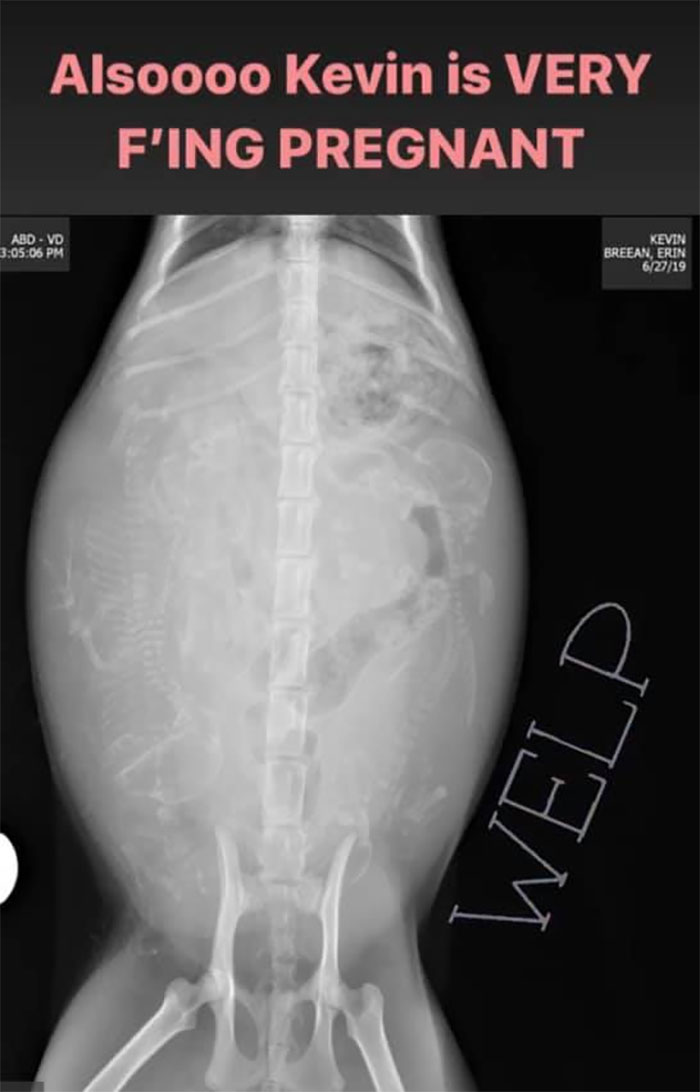

At first, it turned out that Kevin was a female. If that wasn’t enough, the vet soon determined that Kevin was pregnant. Being a huge animal lover, Erin decided to take in the kitty and help her bring her litter into this world. To everyone’s delight, Erin also documented the entire thing and the diary turned out to be absolutely wholesome.

Eventually, Erin started opening her office door for her and figured if she wanted to come in, she would. She did. “She took a few laps around my office and laid down in the hallway like, ‘This is my house now’. I closed my office door, put her in our bathroom, and found a vet that would see us the next day to see if she was chipped. She wasn’t, and that’s when we found out that she was a girl and pregnant,” Erin explained.

“The date on the right is the estimated age the vet put down for Kevin. No, this isn’t a conspiracy, lol. The date of the visit was cut off so I could squish the pic in an Instagram story”